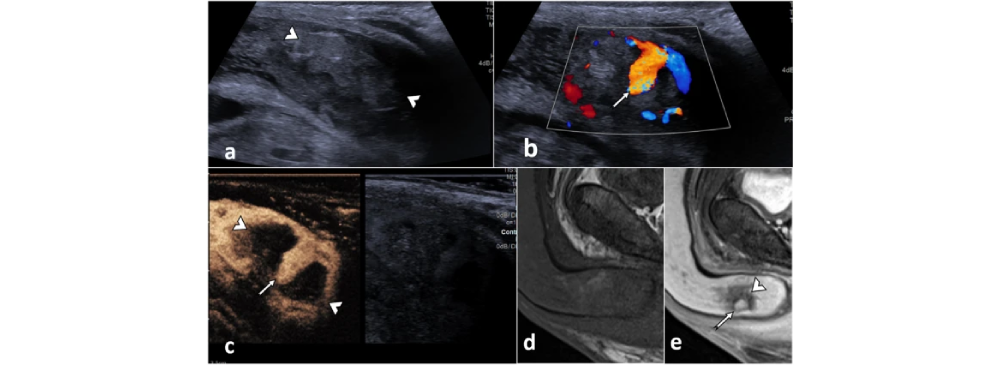

This test is completely non-invasive, safe, and painless. Using ultrasound waves, it allows radiologists to study how well blood circulates through the penile tissues both at rest and during stimulation. By analyzing this vascular performance, doctors can identify whether erectile dysfunction is linked to poor arterial inflow, venous leakage, or structural deformities such as Peyronie’s disease. The results provide clarity not only for men experiencing difficulties but also for specialists who want to design an accurate and personalized treatment plan.

During the procedure, a specialized ultrasound probe with Doppler imaging is used to study penile arteries and veins. A cooling gel is applied to the area for smooth imaging, and high-frequency sound waves are transmitted through the tissues. These signals create real-time images of blood flow. In some cases, to mimic a natural erection and get an accurate assessment, a small dose of medication may be injected. This allows doctors to evaluate vascular function under stimulated conditions, ensuring that no detail is missed.

A Penile Doppler report format typically measures peak systolic velocity (PSV), end diastolic velocity (EDV), and resistive index (RI). Normal values usually include a PSV greater than 30 cm/s and minimal EDV, which indicates good arterial inflow and no significant venous leak. However, interpretation should always be done by a radiologist or urologist based on the patient’s overall condition.